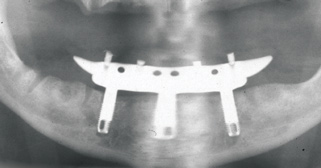

Fig 1. 81-year-old patient had severe mandibular atrophy from many years of denture wear and had a history of inability to manage a mandibular prosthesis.

Figure 1

Fig 2. Four vertical machined-surface osseointegrated implants placed in 1983 penetrated the inferior cortex up to 3 mm to 4 mm in depth, immediate postoperative.

Figure 2

The Toronto Conference in 1982, chaired by Professor George Zarb and presented by Professor Per-Ingvar Brånemark, was a seminal event that changed edentulous treatment planning concepts irrevocably. No longer was it necessary to rebuild lost bone through grafting alone in either arch. The severely atrophic mandible, for example, could be treated with as few as four implants used to support a bone-sparing prosthesis through integrated tooth analogs, as demonstrated in Figure 1 through Figure 3. Here, an 81-year-old patient presented with severe mandibular atrophy (Figure 1) from denture wear since a very young age and had a history of being unable to manage a mandibular prosthesis despite numerous attempts at new denture construction. Four vertical machined-surface osseointegrated implants were placed in 1983 by Professor Brånemark, and all four penetrated the inferior cortex up to 3 mm to 4 mm in depth, as shown on the immediate postoperative panoramic film (Figure 2). At 4 years and 5 months, reparative bone had formed to the apices of all implants (Figure 3), and all of them remained in uncompromised function until the patient passed away at age 90.